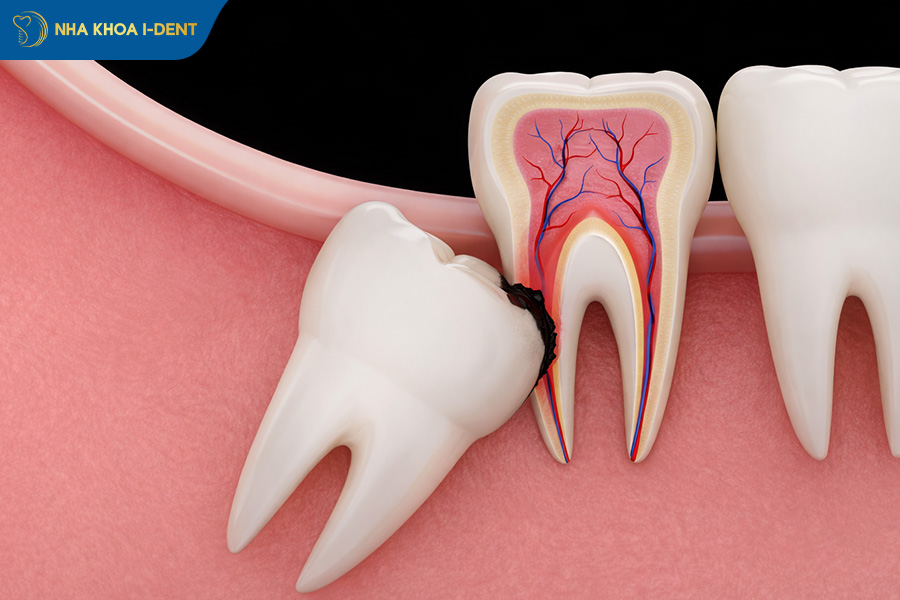

2.3. Gây chèn ép và tiêu chân răng số 7

Việc trì hoãn nhổ răng khôn mọc lệch, mọc ngầm còn là nguyên nhân hàng đầu dẫn đến tình trạng tiêu xương hàm nghiêm trọng. Khi răng khôn mọc không đúng vị trí, chúng tạo ra các “túi lợi” đọng thức ăn, gây viêm nhiễm và phá hủy ổ xương xung quanh. Nguy hiểm hơn, tình trạng viêm nha chu do răng số 8 có thể lan rộng, làm tiêu vách xương nâng đỡ và gây lung lay răng số 7 kế cận.

- Răng khôn số 8 mọc lệch không nhổ có thể gây tiêu chân răng số 7.